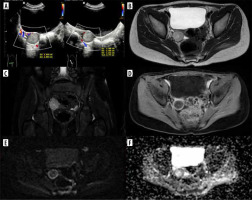

Figure 5

Exams of the right ovary metastasis in Patient no. 1. A) Initial ultrasound; axial and sagittal plane. B-F) Pelvic magnetic resonance imaging. B) FSE/T2, axial plane, C) STIR, coronal plane, D) WATER/T1 post-Gd, axial plane, E) DWI, axial plane, F) corresponding ADC map

Ultrasound (US) at our institution identified 2 solid lesions with suspected metastatic characteristics alongside the primary foot tumour: one in the right ovary (oval, relatively homogeneous, with medium-high echogenicity, approximately 20 × 16 × 16 mm – Figure 5A) and the other one in the right fifth intercostal space (hypoechoic, with slightly polycyclic outlines, about 14 × 11 × 7 mm). Pelvic MRI corroborated the presence of these findings and additionally detected metastasis in the left gluteus maximus muscle and a suspicious left inguinal lymph node. The ovarian metastasis exhibited peripheral diffusion restriction and contrast enhancement (Figures 5B-F).

RMS metastases to the ovary rarely cause symptoms [22]. In our patient, a lesion in the right ovary was incidentally detected during abdominal US before the initiation of treatment. Both US and MR images did not show specific features. However, with the knowledge of the primary tumour in the foot, the nature of the focal lesion in the ovary became evident.

Figure 6

Exams of Patient no. 2 with tumour plugs in the vessels. A, B) Computed tomography (CT) shows partial sclerotic tumour plugs in many vessels, including uterine venous plexus. A) Coronal plane, B) axial plane. C) CT scan shows chondrosarcoma of the sacrum; axial plane. D) MRI study; STIR, coronal plane